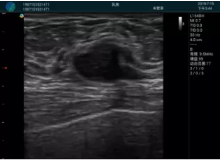

清晰顯示腺體內低回聲快影,邊界清晰,包膜較光滑

確定進(jìn)針路徑并實(shí)時(shí)監測抽吸針與腫塊位置關(guān)系

抽吸針進(jìn)入腫塊內部進(jìn)行旋切

抽吸過(guò)程中可見(jiàn)腫塊明顯縮小,并根據腫塊位置改變針道位置

抽吸旋切后再進(jìn)行超聲復查,原腫塊區域未見(jiàn)殘留組織及出血